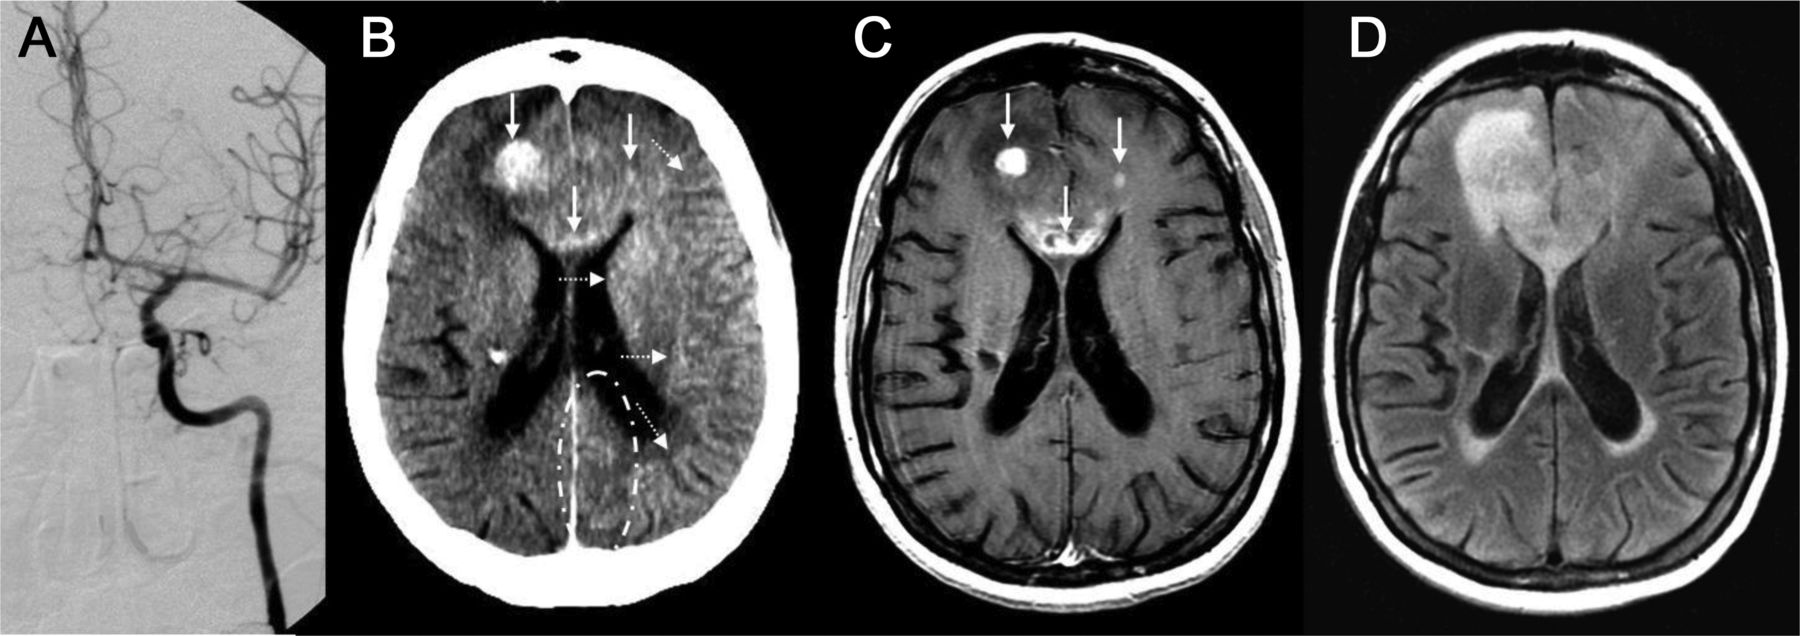

一位39岁的女性接受了左颈内动脉(ICA)血脑屏障破坏(BBBD) (A),与(预期)合成左半球皮质增强超声造影CT(摄影)(B,虚线箭头),可能有轻度左侧皮质增强大脑后动脉(PCA)分布,有一个著名的离开沟通后动脉供应左侧PCA(点划轮廓,B)。Postcontrast t1加权磁共振成像(C)显示,病灶增强,对应于这些可视化post-BBBD摄影(实心箭头,B, C),与适量的右额叶病灶周围水肿和证据传遍的胼胝体膝fluid-attenuated反转恢复核磁共振(D)。